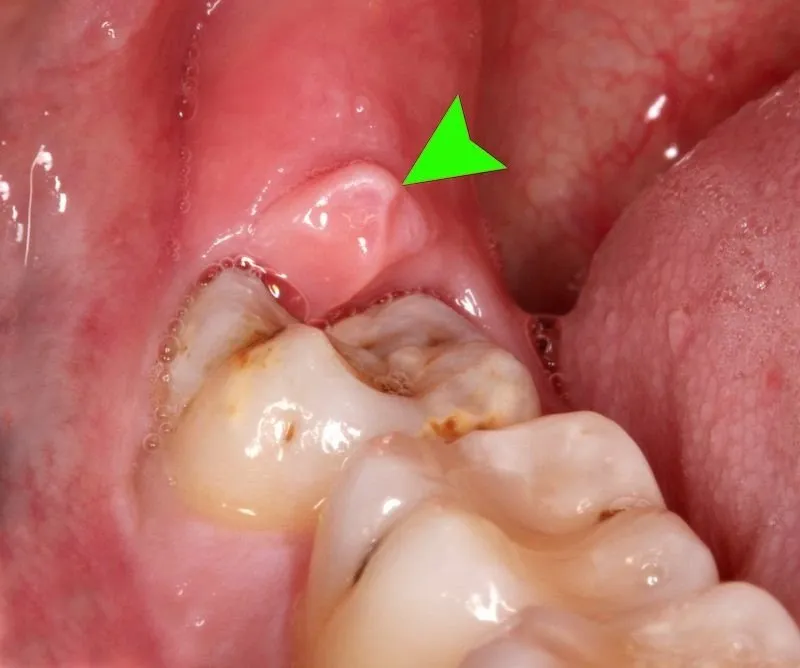

Viêm lợi trùm là một trong những bệnh răng miệng phổ biến nhiều người mắc hiện nay. Người mắc phải sẽ cảm thấy khó chịu và đau

Bệnh viêm lợi trùm là bệnh mà bất kì ai cũng có thể gặp phải, đặc biệt ở bà bầu. Bà bầu mắc phải sẽ cảm thấy